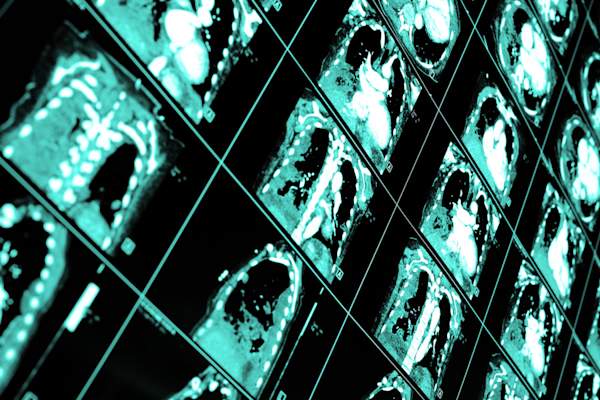

你的症状可能会有所不同从吸烟者的肺癌

在一般情况下,从不吸烟者往往不显示肺癌的持续性咳嗽或喘息,气短通常的迹象,咳血。因为从不吸烟者通常会更健康(和有更好的肺活量),他们经常会去医生那里做什么都没有做他们的肺,像骨头的疼痛或严重的头痛是真的迹象的症状,症状,他们的癌细胞已经扩散到利维博士说,他们的身体的其他部位。虽然这是可怕的听到的,记住,这是为广大肺癌患者也是如此。这是一种疾病,可令人沮丧很难早期发现。

巨蟹座:巨蟹的分型往往是不同的

许多从不吸烟者得癌症全线最常见的类型,这也是非小细胞肺腺癌。极少数情况下,这样做不吸烟者得小细胞或鳞状细胞癌(在吸烟者中较为常见)。其原因可能在于体内毒素的从不吸烟者已经暴露量。“鳞状细胞和小细胞肺癌往往有更多的突变,”金沙博士解释说。

这是更不可能得到这些癌症没有显著毒素暴露,导致更大的压力对细胞和DNA,导致DNA中的错误和突变。如果你还不知道,问你的肿瘤学家的亚型是什么,建议金沙博士。明知将决定你的治疗方案,并帮助您的提供商弄清楚,如果你是靶向治疗或临床试验的候选者。

你的肿瘤有明显的标志物

“有时候,在一个从未吸烟者肺癌的行为不同于在吸烟者和具有不同的基因组成,”利维博士说。这些ddifferences不符合你与生俱来的 - 它们发生在肿瘤的细胞,并能活检期间来识别变异基因。

迄今为止,科学家已经确定了几个,这些遗传标记,其中包括EFGR,ALK,ROS-1,其中的DNA变化是简单的。在许多EFGR突变,例如,突变发生只是在受影响的细胞,而不是在非癌的人,使其更容易与目标治疗。